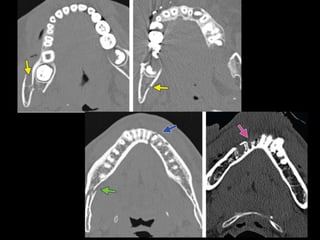

FRACTURA DENTOALVEOLAR

• Dislocación dentaria

– Contusión, subluxación y luxación

– Intrusión o extrusión

• - Fractura de corona

– Fractura del esmalte

– Fractura del esmalte con dentina

– Fractura expuesta

• - Fractura radiculares (raíz)

– Fractura cervical

– Fractura media

– Fractura apical

FRACTURA DENTOALVEOLAR • Dislocacióndentaria – Contusión, subluxación y luxación – Intrusión o extrusión • - Fractura de corona – Fractura del esmalte – Fractura del esmalte con dentina – Fractura expuesta • - Fractura radiculares (raíz) – Fractura cervical – Fractura media – Fractura apical

• #26 Because of the abundance of bacteria in the mouth, a fracture of the alveolar process is treated as an open fracture in which there is a breach of the overlying mucosa necessitating surgical débridement and prophylactic antibiotics. Potential complications of alveolar process fractures include dental root avulsion, crown or root fracture, dental intrusion or extrusion, and malocclusion